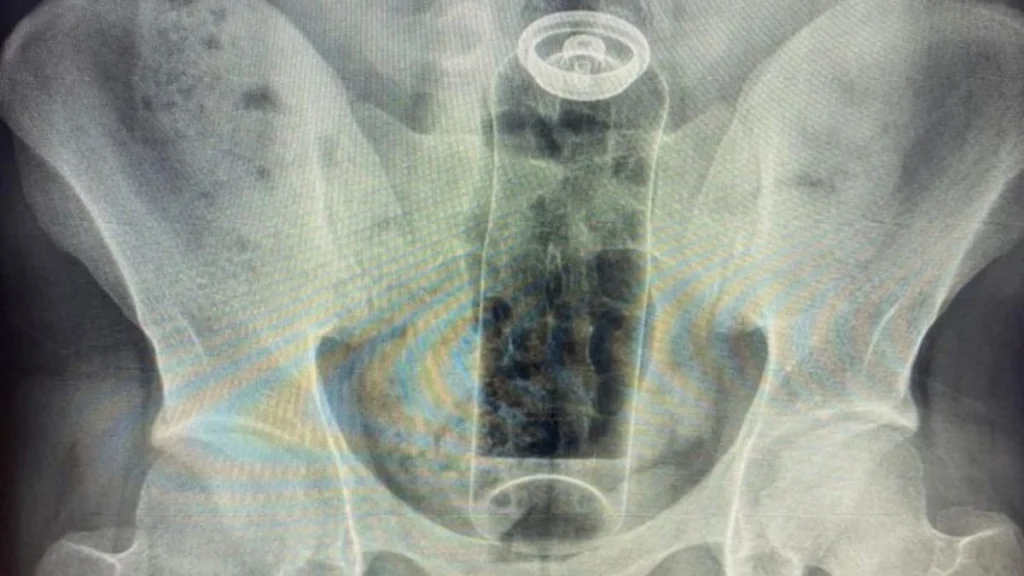

Segundo o especialista, o paciente relatou que o incidente ocorreu durante uma “brincadeira” sexual. A embalagem acabou subindo para o reto e, após tentativas frustradas de retirá-la em casa, o jovem buscou ajuda médica.

O médico explicou que o intestino possui movimentos peristálticos (contrações involuntárias) que, somados ao vácuo criado na região, podem “sugar” o objeto, dificultando sua remoção manual.